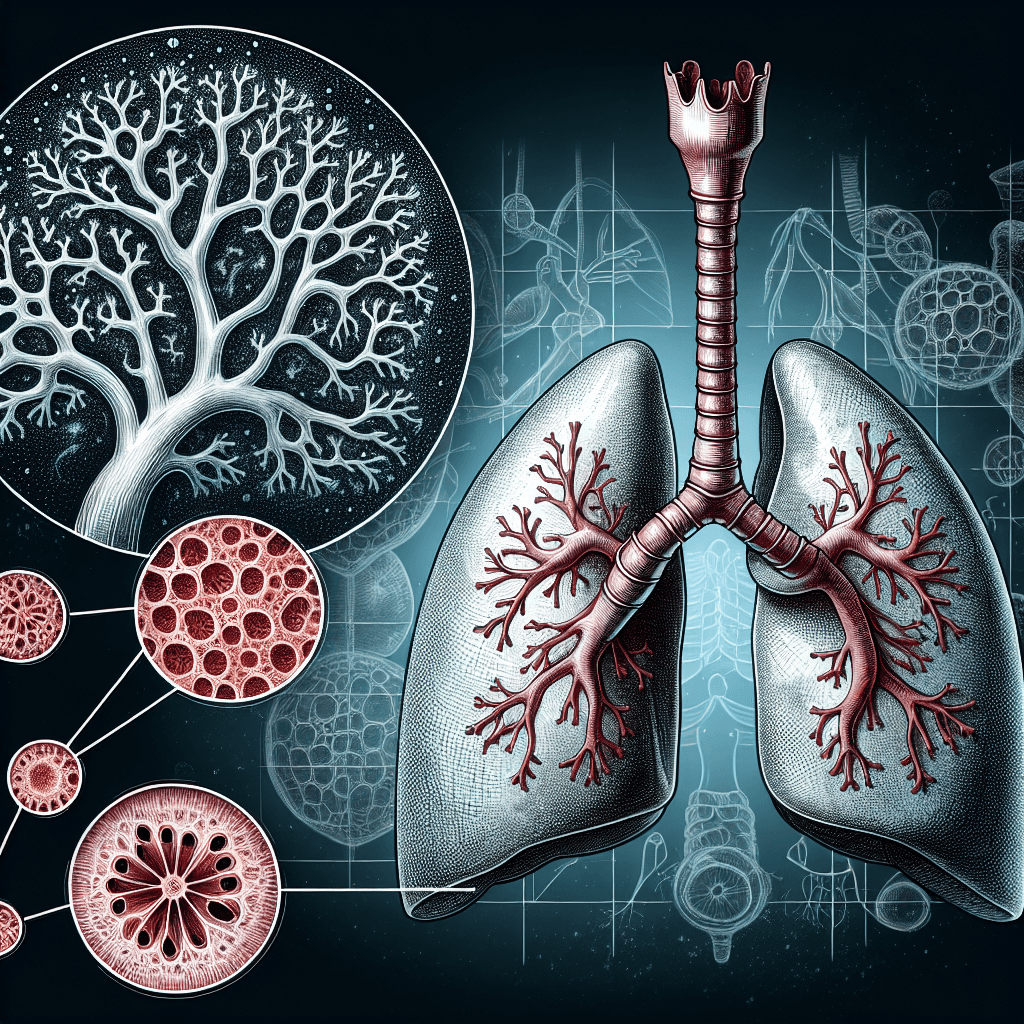

- CEFRレベル: B2(中上級)

- 専門的な分野でも使われる単語で、日常会話でそこまで頻繁には登場しませんが、知識・教養レベルの英単語としては中上級の学習者が知っておくとよいでしょう。

- 形容詞なので、名詞の前に置いて使われることが多く、動詞のような時制による活用はありません。

- 他の品詞例:

- respiration (名詞): 呼吸

- respire (動詞): 呼吸する

- respirator (名詞): 人工呼吸器

- respiration (名詞): 呼吸

- 語源・構成

- 接頭語「re-」: 「再び、もう一度」という意味

- 語幹「spir / spirare」: ラテン語「呼吸する(breathe)」

- 接尾語「-atory」: 「~に関する、~の役割を持つ」を表す形容詞化の接尾語

- 接頭語「re-」: 「再び、もう一度」という意味

- そこから「respiratory」は「呼吸に関する」という意味になります。

- respiratory system(呼吸器系)

- respiratory infection(呼吸器感染症)

- respiratory tract(呼吸器官・気道)

- respiratory function(呼吸機能)

- respiratory rate(呼吸数)

- respiratory therapy(呼吸療法)

- respiratory distress(呼吸困難)

- respiratory disease(呼吸器系の病気)

- upper respiratory tract(上気道)

- respiratory protective equipment(呼吸用保護具)

- 語源はラテン語「respirare(再び息をする)」から来ています。「re- (再び) + spirare (息をする)」が由来で、英語では「呼吸に関する」というニュアンスで使われます。

- 医学や生物学の文章で使われる際はフォーマルな響きがあり、日常生活では「breathing」という言い方のほうがカジュアルになります。

- 形容詞なので、名詞の前に置いて「respiratory system」のように修飾します。可算・不可算の区別は名詞ではないためありません。

- フォーマル/カジュアルの違い:

- 医療や学術論文、専門書では「respiratory」が一般的。

- 会話で単に「breathing」に置き換える場合も多いですが、正確性を求めるときは「respiratory」と言います。

- 医療や学術論文、専門書では「respiratory」が一般的。

呼吸の,呼吸作用の,呼吸のための

呼吸の,呼吸作用の,呼吸のための

解説

respiratory

1. 基本情報と概要

単語: respiratory

品詞: 形容詞 (adjective)

意味(英語): relating to or affecting breathing or the organs of the body that are used for breathing

意味(日本語): 呼吸や、呼吸に関わる器官に関連するさまを表す形容詞です。たとえば「呼吸器系の~」というときに使います。医療や生物学の文脈でよく用いられ、病気や治療、器官の働きを説明するときにも出てきます。

活用形

2. 語構成と詳細な意味

よく使われるコロケーション(共起表現)10選

以上が形容詞 respiratory の詳しい解説です。医療や生物学の分野で多用されるため、専門的な文章を読む際にはよく出会う単語です。しっかり覚えておくとスムーズに理解や表現に活かせます。

呼吸の,呼吸作用の,呼吸のための